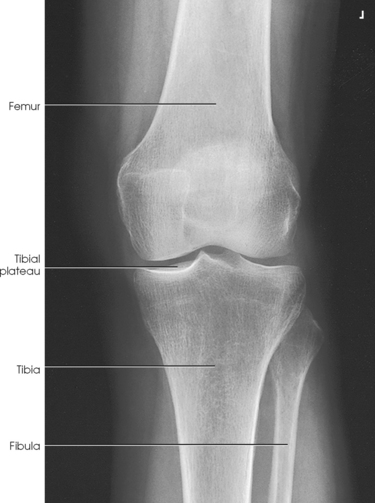

Structures shown: The resulting image shows an AP projection of the knee structures (Fig. 6-121).